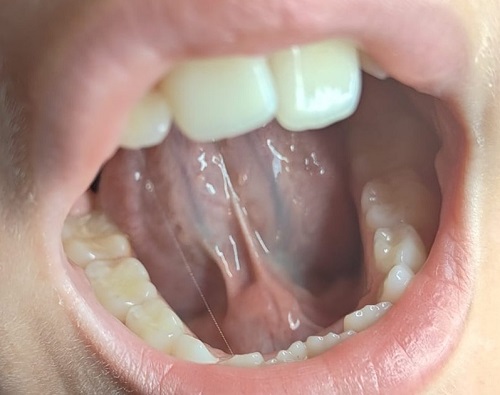

Dos semanas después de la primera consulta la clínica persistía, con dolor y aumento del tamaño de la tumoración con la ingesta. En la exploración intraoral se apreciaba el conducto de Wharton inflamado, asociando, cerca de la salida, una tumoración dura y dolorosa a la palpación, de 3-4 cm. (Figura 1). Ante la sospecha de sialolitiasis submaxilar se solicitó una ecografía y se inició un tratamiento conservador con masaje local, aplicación de calor local y empleo de sialogogos.

Figura 1. Tumoración submandibular a nivel de la salida del conducto de Wharton